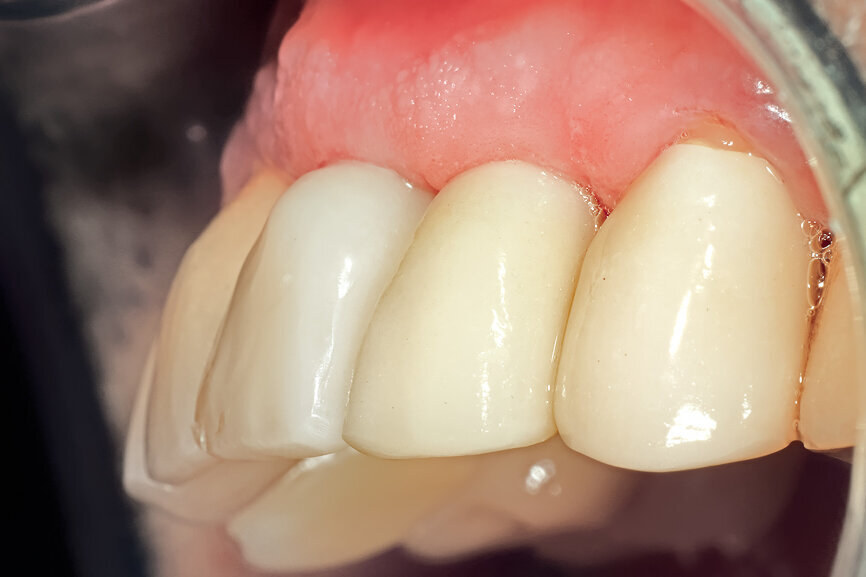

Fig. 29: The definitive restoration exhibited excellent retention of the soft-tissue profile.

Fig. 30a: The occlusal view revealed the volume maintained with

the soft-tissue cervical contours (a), and the lateral retracted view revealed an excellent soft-tissue emergence profile (b).

Fig. 30b: The occlusal view revealed the volume maintained with

The initial plan was for immediate extraction, immediate placement and immediate restoration. Therefore, it was essential to measure the implant’s stability with an objective technology, RFA, which provides an ISQ value utilising an implant-specific SmartPeg (Osstell; MEGA ISQ, MegaGen). The baseline ISQ value (76) confirmed sufficient initial stability to place an immediate restoration (Fig. 25). The prefabricated CAD/CAM abutment was then secured to the implant, and a postoperative periapical radiograph confirmed successful sub-crestal placement for this platform-switched design (Fig. 26a). The transitional acrylic restoration was then placed and examined for any occlusal interferences (Fig. 26b). It was important that the restoration be out of occlusion to avoid premature forces that could complicate integration. The soft-tissue contours were excellent, and no sutures were required, since no flap was raised (Figs. 26c & d). After a period of eight weeks, the implant stability was measured to be at 80 ISQ, confirming that the integration process had continued to progress successfully and that the implant was ready for the definitive restoration. An intra-oral scanner and scanning abutment were then utilised to capture the position of the implant and soft-tissue emergence profile. The post- operative CBCT scan revealed the intact crescent shape of the root membrane (Figs. 27 & 28). The definitive restoration was then delivered and exhibited excellent retention of the soft-tissue profile (Figs. 29 & 30).